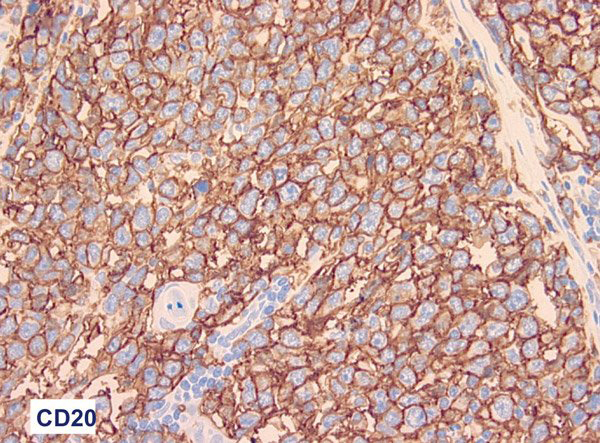

© Pr J. Audouin (service d'anatomie et de cytologie pathologiques, Hôtel-Dieu), La Revue du Praticien

Les cellules tumorales expriment CD20 sous forme d’une vive positivité membranaire. Voir : Molina TJ. Classification des lymphomes. Rev Prat 2010;60:48-52.